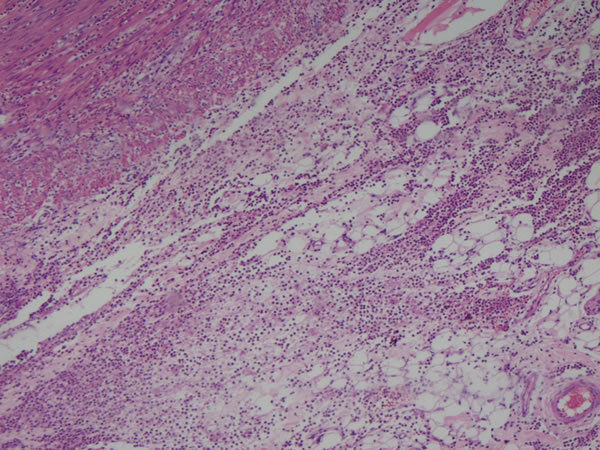

Image:

Intestino grosso Neoplasia - adenocarcinoma de cólon Células neoplásicas invadiram a camada muscular lisa |

Intestino grosso Neoplasia -adenocarcinoma de colon Células neoplásicas invadindo submucosa Notar as células normais no canto superioe esquerdo |

| A | Intestino grosso Neoplasia - adenocarcinoma de colon bem diferenciado Outros achados: necrose, infl. aguda e crônica Lado D normal Lado E neoplásicas |